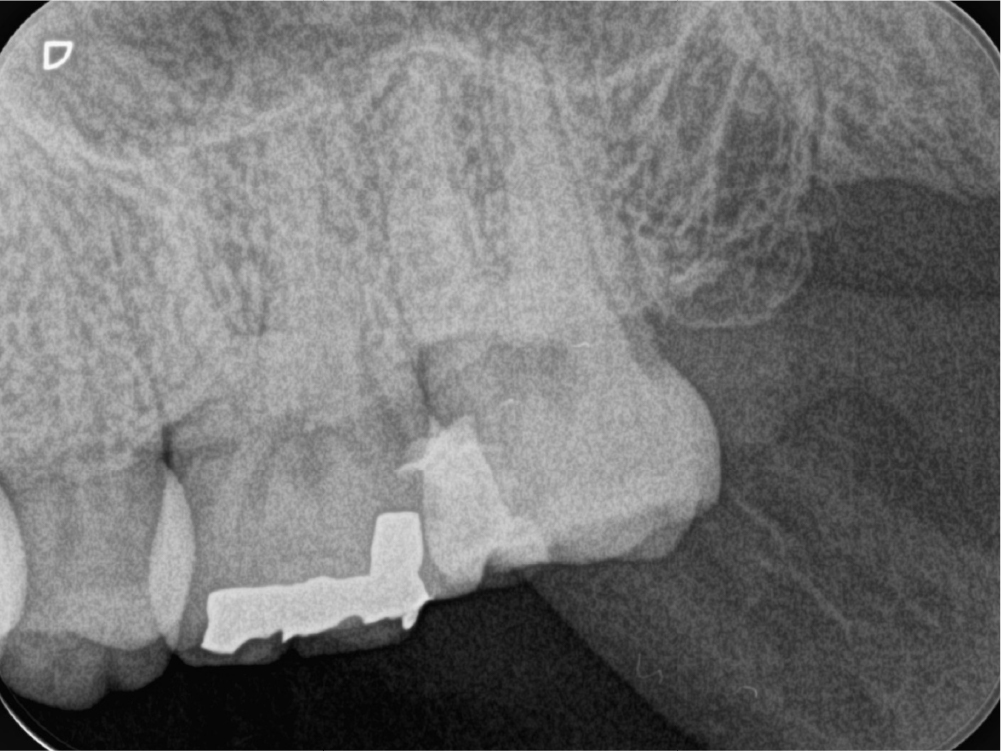

case:4

再治療で改善しない腫れに対し、外科的歯内療法(歯根端切除)で治癒したケース

根管治療の症例

術前

術後9ヶ月

歯ぐきの腫れと膿の出口(サイナストラクト)があり、検査により原因歯を特定しました。再根管治療で根管内の感染コントロールを試みましたが症状が改善せず、CTで病変範囲を精査。

近心根切断面

遠心根切断面

上記の写真は、歯根端切除後の切断面を顕微鏡を用いて精査している写真です。 歯内療法の専門医が外科的歯内療法(歯根端切除)を行い、術後の経過で骨の回復が確認でき、良好な治癒につながりました。

年齢性別 30代・男性

主訴 右下の銀歯のところが腫れている/膿が出る(サイナストラクト)

治療部位 右下6番

治療内容 瘻孔トレースで原因歯特定 → 再根管治療 → 改善乏しく外科的歯内療法(歯根端切除・逆根管充填)

治療回数 1回(根管治療含めると3回)

リスク副作用 外科処置後に腫れ・痛み・出血が生じることがあります。状態によっては治癒が得られず、追加治療や抜歯が必要になる場合があります。

担当医からのコメント

再根管治療だけでは改善が難しいケースでも、外科的歯内療法という選択肢で歯を残せる場合があります。外科を含めた難易度の高い処置まで一貫して対応できるのは、歯内療法を専門に診ている強みの一つです。「抜歯しかない」と言われた歯でも、状態次第では保存の可能性があります。